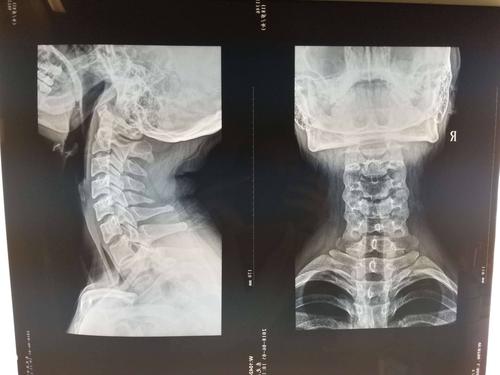

颈椎正侧位备孕可以拍片吗

根据现有的辐射原理,主要分为CT、x射线以及拍片。x射线电离辐射力强辐射量小,而x射线的电离辐射并不直接而确定。

颈椎拍片是怎么处理